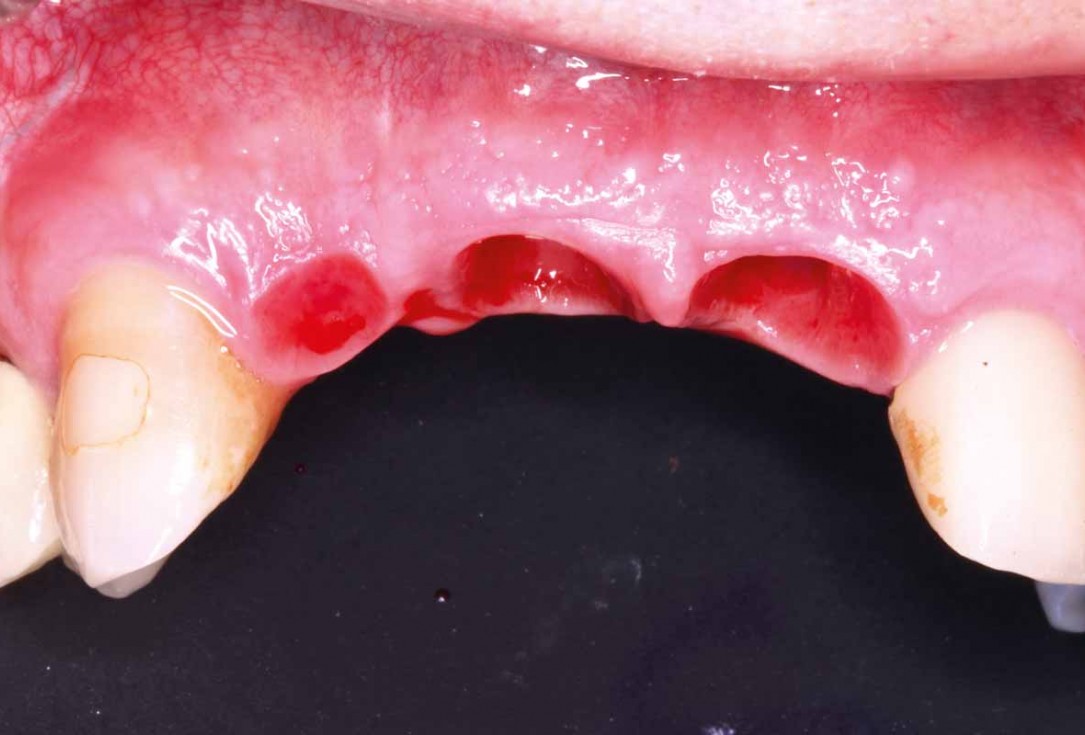

16/27 - 12 weeks after surgery: showing partial exposure of the healing abutments and satisfactory convexity

GBR and soft tissue augmentation with cerabone® and mucoderm® - H. Maghaireh & V. Ivancheva